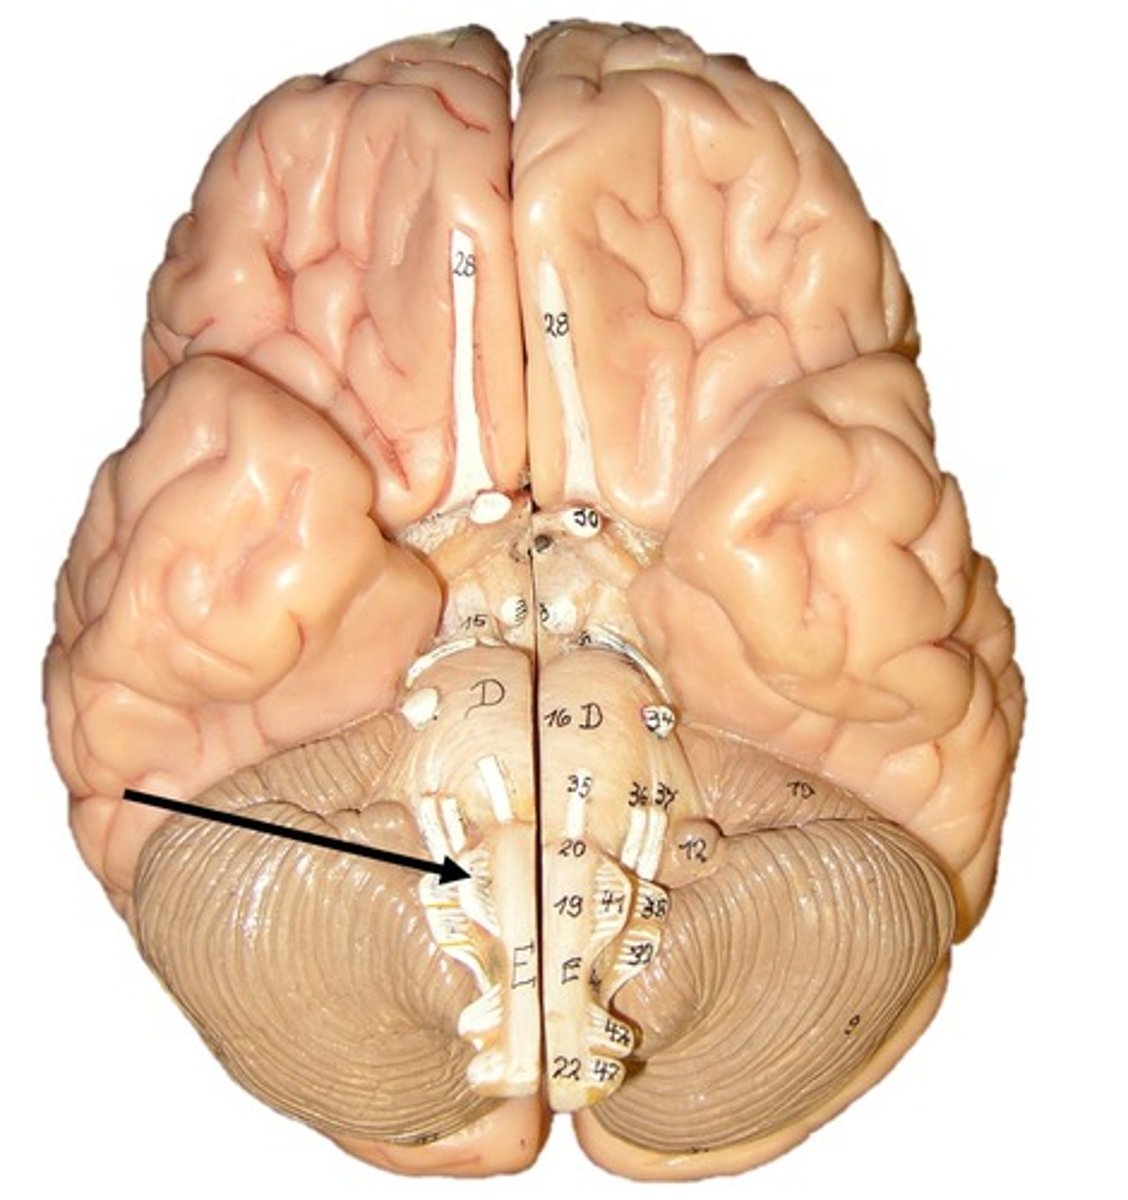

Cerebellum

anterior lobe of cerebellum

posterior lobe of cerebellum

vermis

cerebellar peduncles

folia

arbor vitae

Primary fissure